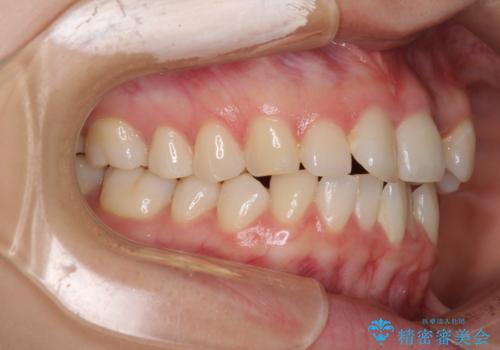

上下前歯が非接触である開咬は、インビザラインによる治療がお勧めではありますが、非抜歯矯正か抜歯矯正か悩む口元であり、途中抜歯矯正に切り替えたときに対応しやすいよう、ワイヤー装置にて治療を行うこととしました。

舌の突出癖の影響もあり、非抜歯矯正で治療開始したものの口元が突出し、唇が閉じにくくなってしまったため、途中で第一小臼歯4本を抜歯ししました。